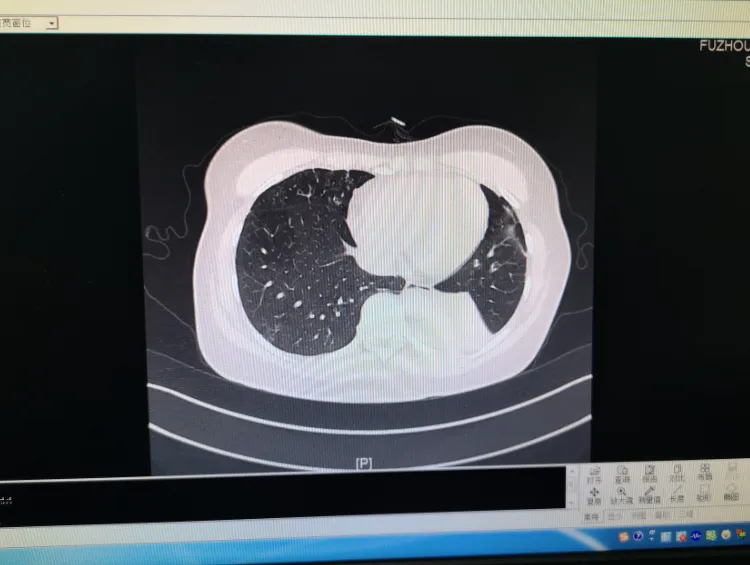

近日,福建省福州肺科医院接诊一例患者,该女子咳嗽两个月未愈,经查确诊为侵袭性支气管肺曲霉菌病。

医生表示,内镜检查时,发现患者肺部有非常严重的痰栓及坏死物,已经堵塞管腔,将坏死物活检后去做病理检查,发现了大量的霉菌。